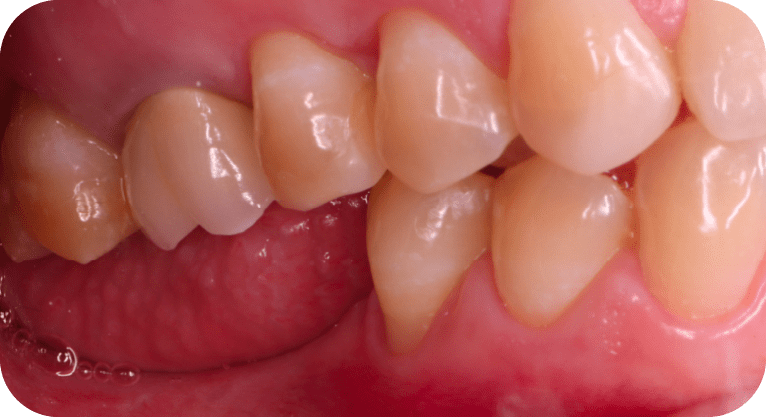

Paciente femenino, “42” años

Tratamiento: Implante dental

El paciente acudió a la clínica tras haber perdido dos molares por caries avanzada, lo que afectaba su función masticatoria. Para restaurar la zona edéntula, se realizó la colocación de implantes dentales en los espacios correspondientes, devolviendo así la capacidad de masticación, previniendo la pérdida ósea y manteniendo la alineación de las piezas adyacentes, con resultados funcionales y estéticos satisfactorios.